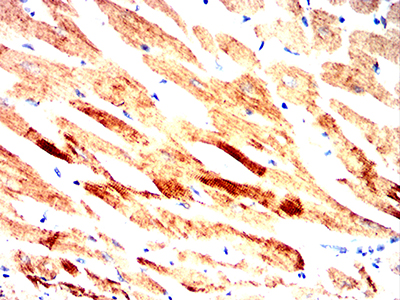

- Immunohistochemical analysis of paraffin-embedded human cervical cancer tissues using SQSTM1 mouse mAb with DAB staining.

- Immunohistochemical analysis of paraffin-embedded human bladder cancer tissues using SQSTM1 mouse mAb with DAB staining.

- Immunohistochemical analysis of paraffin-embedded Mouse Heart using SQSTM1 mouse mAb with DAB staining.

- Immunohistochemical analysis of paraffin-embedded Rat Heart using SQSTM1 mouse mAb with DAB staining.

- Immunohistochemical analysis of paraffin-embedded Rabbit Heart using SQSTM1 mouse mAb with DAB staining.